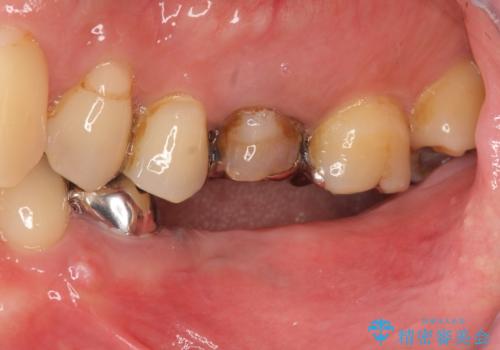

[ インプラント治療 ]失った奥歯を回復したい